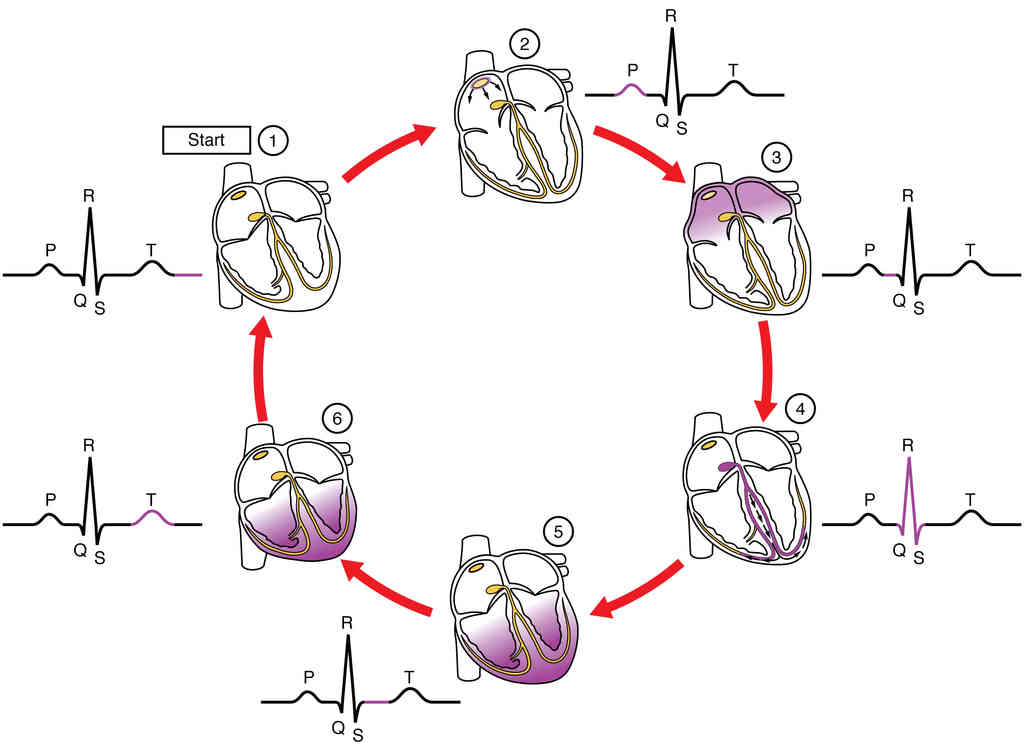

This page is under construction. For now, it is just a resource of the images found in the OpenStax Anatomy and Physiology Handbook. It wil slowly change into a revision tool. Each slide has a number. Use this to refer to the slide. When completed, it will have an unlabelled section, with labelled slides in parallel. On the unlabelled slides, write your answer and use the labelled slide to assess yourself. Keep track by also noting the number on each slide. Improvement at each attempt is important, more so than full marks on a first attempt.